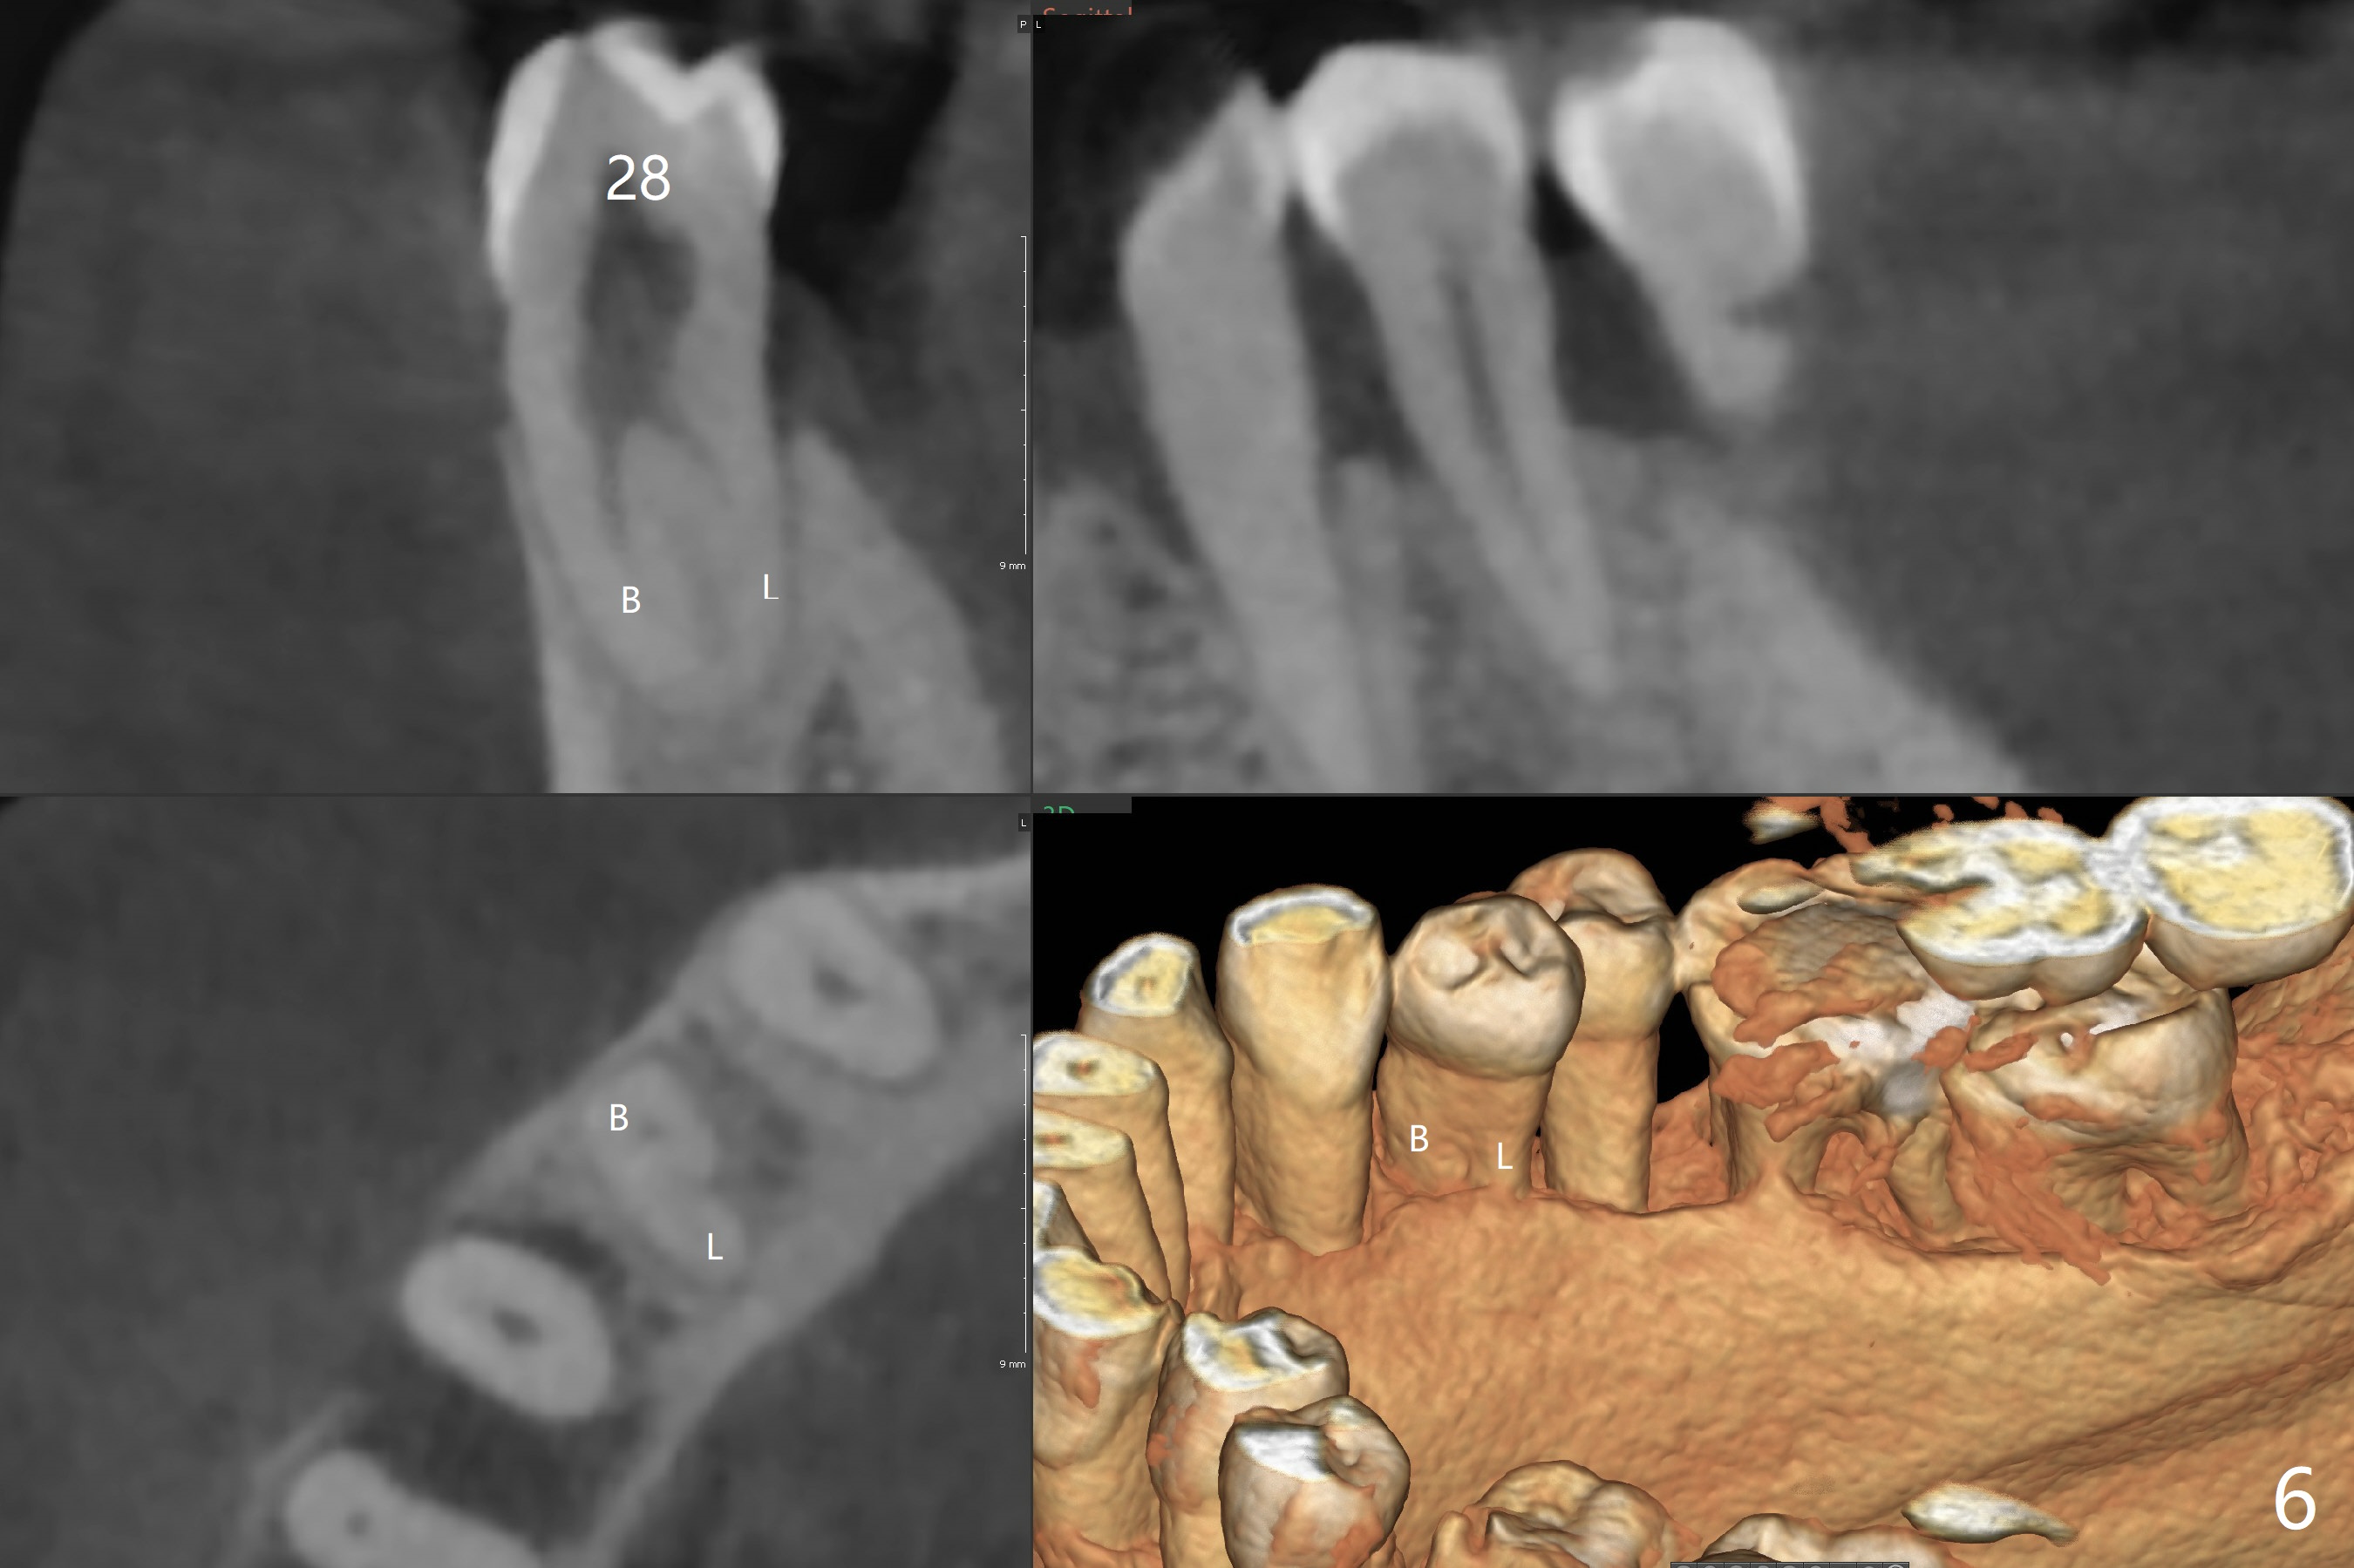

A 60-year-old man (smoker, 1/3 to 1/2 ppd) with large DO amalgam at #30 develops pain and mild swelling apparently apical to #29 (Fig.1-3). Both teeth (having fused PARL (periapical radiolucency) *) have mild percussion with the tooth #29 having higher mobility. CBCT shows apical defect (Fig.3 >). Three weeks earlier, the tooth #19 had much more severe infection with a similar apical defect (Fig.4 >). Combined with history of repeated infection associated with #30, the tooth is extracted with difficulty in obtain sound anesthesia. Socket preservation is performed instead of immediate implant (Fig.5 (*: Vanilla Graft)). CBCT makes it easy to diagnose 2 canals at #28 (Fig.6 as compared to Fig.2). Pain gradually decreases 3 days postop. In fact he has hypertension and smokes.

The bone seems to be wide to hold a 5x11.5 mm implant if it is placed early post extraction (Fig.7). Probably due to smoking, the socket appears to heal slow (Fig.8,9). There is mild palpation pain in the buccal vestibule. The tooth #29 remains mobile. The patient is scheduled to return for follow up in 2 months. A 5x5 cm scan is taken for the lower right posterior area for guided surgery.